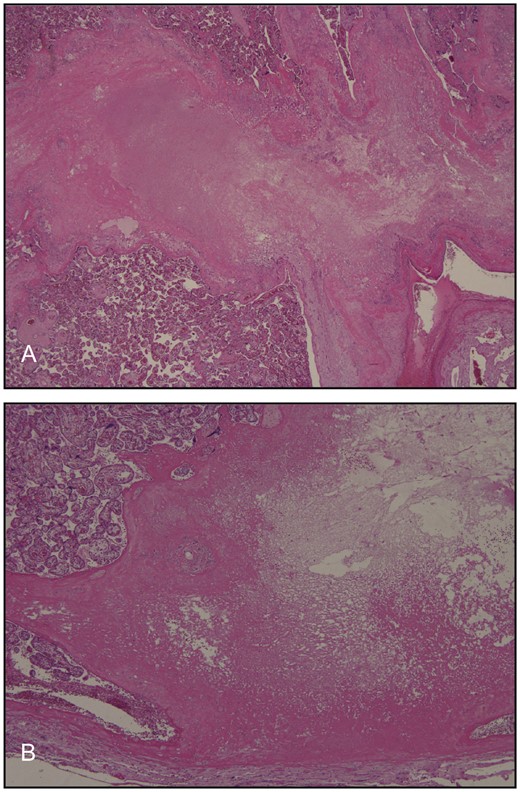

Microscopy confirmed the presence of focal infarcts, but no massive fibrin depositions were seen (Fig. 3A and B). There were no particular vascular abnormalities or apparent thrombi were detected. The placental villi were of appropriate maturity for gestational age and the villous vessels showed no structural abnormalities (Fig. 4A). No signs of chorioamnionitis were detected (Fig. 4B). No signs of funisitis or structural abnormalities were identified in the umbilical cord, which had two arteries and one vein (Fig. 4C). Using immunohistochemistry, the villi showed minimal immunoreactivity for complement split product C4d (Fig. 5).

Histologic images corresponding to the placental infarcts shown in Fig. 2A.